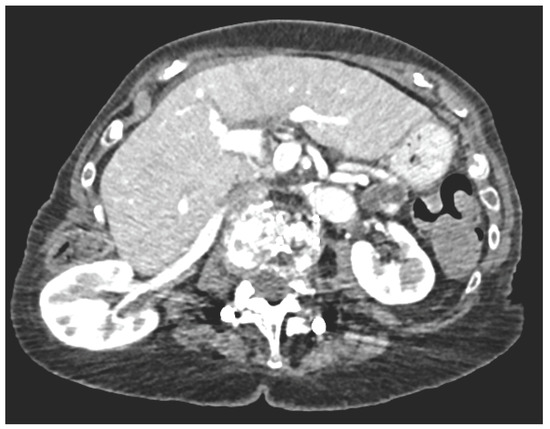

Biochemistry and inf lammatory markers were normal. CT imaging demonstrated a right renal flank hernia through the retroperitoneum into the subcutaeneous tissue (Figure 1A,B). The renal artery and vein were significantly stretched, without evidence of acute pathology. There was no evidence of hydronephrosis or delayed nephrogram.

Figure 1.

A. Axial CT. B. Sagittal CT.